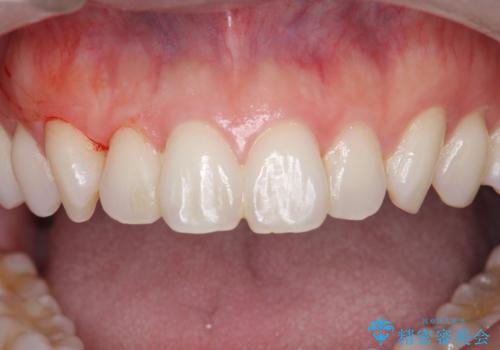

歯ぎしりが気になる。

- 寝ている間に歯ぎしりをしている気がするとの事で来院。

過去にナイトガードを使用したことがあったが穴が空いてしまったそうです。

ナイトガードを使用することによって歯がすり減る(寝ている時の歯ぎしりなど)事を防いでくれます。